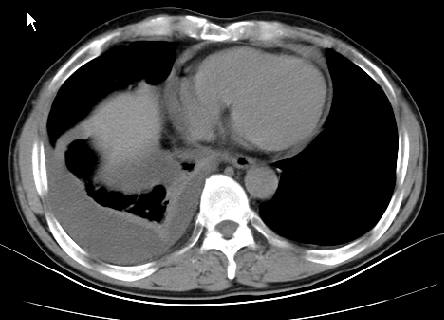

以下是引用草之原在2009-5-2 19:29:00的发言:[br]1.考虑右侧中心型肺ca纵膈淋巴结转移,双侧胸腔积液及右侧叶间裂积液,心包积液。[br]2.两肺上叶病灶,纵膈窗显示部分病灶硬化,考虑:结核。[br][br] [br]

以下是引用ct诊断高手在2009-5-2 19:08:00的发言:[br]我考虑右侧中央型肺癌 伴右肺节段性不张,两肺及纵隔淋巴结转移,右侧胸腔积液。

以下是引用zjzjr在2009-5-2 20:16:00的发言:[br]肺结核,转移瘤.纵隔淋巴结转移或淋巴瘤,右侧包裹性积液、斜裂积液。心包积液。